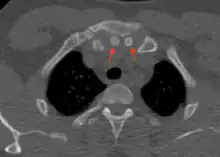

Axial computed tomography showing the episternal ossicles (red arrows)

The episternal ossicles are oval-shaped bones that are occasionally found at the superior and posterior border of the manubrium. The episternal ossicles were first described by Cobb in 1937.[2] They may be present unilaterally or bilaterally.[3] Its size ranges from 2–15 mm depending on individuals.[4] These ossicles are asymptomatic and does not cause any harm, although it may be diagnosed as fracture, vascular ossification or calcified lymph nodes.